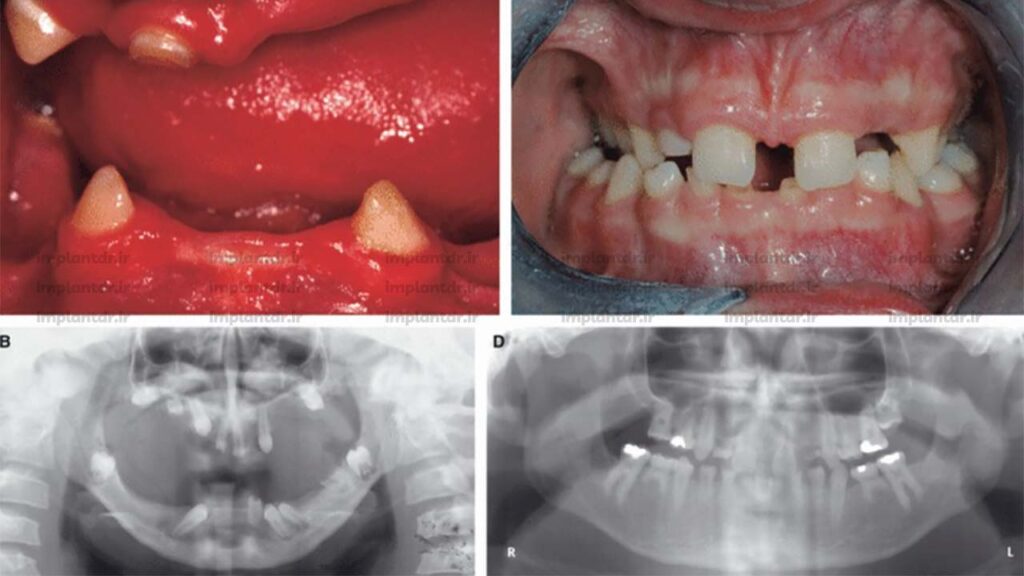

بی دندانی مادرزادی به وضعیتی گفته می شود که یک یا چند دندان به صورت طبیعی تشکیل نشده باشند. این مشکل می تواند تنها در چند دندان (به نام هایپودنتیا) یا در تمام دندان ها (به نام آنودنتیا) دیده شود.

در حالت عادی، انسان ۲۰ دندان شیری و ۳۲ دندان دائمی دارد. اما در افرادی که دچار فقدان مادرزادی دندان هستند، جوانه دندانی در برخی یا تمام نواحی فک تشکیل نشده است و به همین دلیل آن دندان ها هرگز رشد نمی کنند.

شدیدترین نوع فقدان مادرزادی دندان است که در آن هیچ دندانی، چه شیری و چه دائمی، رشد نمی کند. این حالت بسیار نادر است و معمولا با اختلالات پوستی و مو مانند سندرم اکتودرمال دیسپلازی همراه است.

بی دندانی مادرزادی ممکن است بخشی از یک سندرم بزرگ تر باشد، مانند سندرم داون، سندرم اکتودرمال دیسپلازی و شکاف لب و کام (کلیفت پالات).